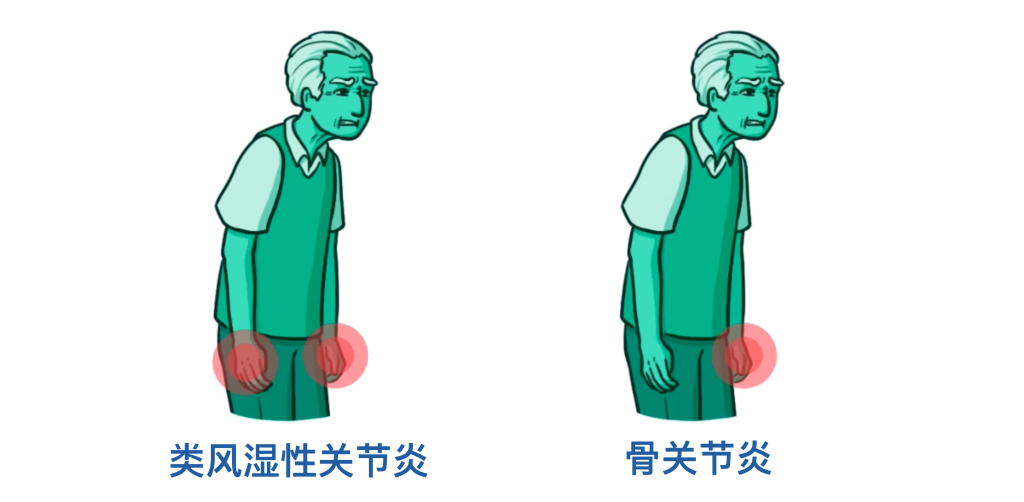

这里有一个临床要点:如果患者的晨僵持续超过30分钟,就需要考虑炎性关节炎,比如类风湿性关节炎。

另一个区分两者的方法是受累关节的分布模式。类风湿性关节炎往往呈对称性,也就是说身体两侧的关节会同时受累;而骨关节炎患者更可能表现为不对称的关节受累。